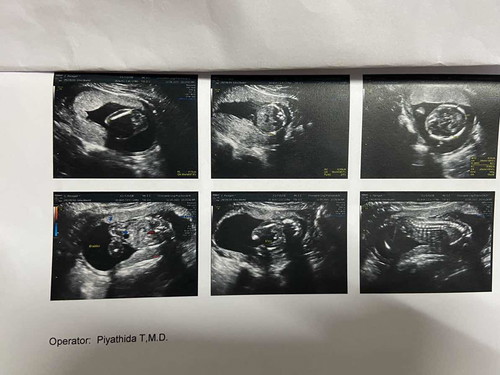

อยากรู้ ผู้ชาย หรือผู้หญิง ช่วยดูหน่อยค่ะ 18 สัปดาห์ 4 วัน

แม่บ้านนี้ว่า 🧒 ค่ะ เหมือนเห็นจู๋น้อง ภาพล่าง ซ้ายมือ